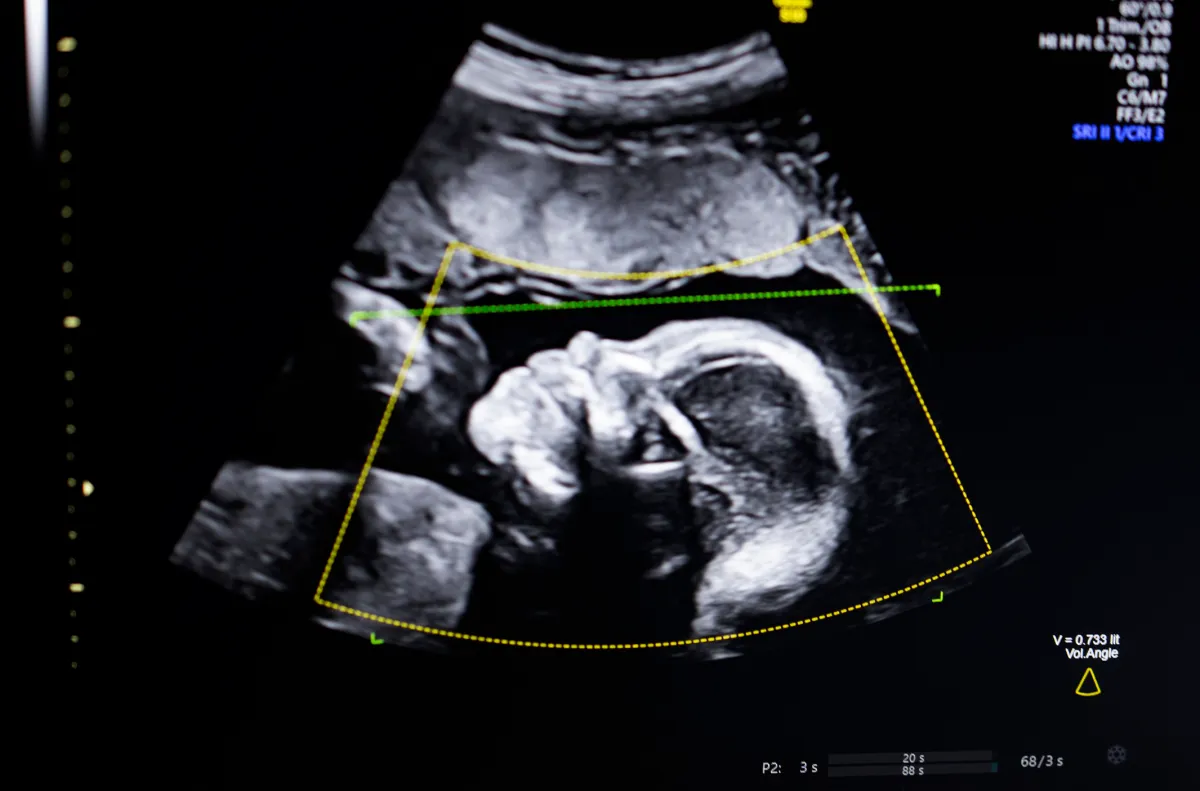

Technologija naudoja kompiuterinės vizijos AI, „kad palaikytų vaisiaus ultragarso kokybės vertinimą, anatominį išsamumą, automatizuotą ataskaitų teikimą ir sklandų integravimą į klinikines darbo eigas“, – „TechCrunch“ sakė Bustami.

Bustami teigė, kad prenatalinis ultragarsas tapo nėštumo stebėjimo „kertiniu akmeniu“, tačiau jo prastos kokybės vaizdai gali sukelti klaidingą diagnozę.

Bustami teigė, kad sunkiausia buvo ne sukurti savo dirbtinio intelekto modelius, kurie buvo apmokyti naudojant įvairius šimtus tūkstančių ultragarsų, bet užtikrinti, kad technologija būtų patikimai veikianti realiame pasaulyje, ypač atsižvelgiant į demografinius rodiklius, kuriuose yra didžiausia tragiškos baigties rizika.